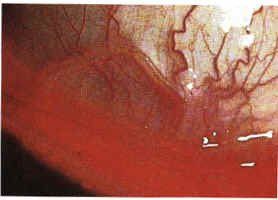

羅阿羅阿絲蟲簡稱羅阿絲蟲,引起羅阿絲蟲病,亦稱為遊走性腫塊或卡拉巴絲蟲性腫塊。成蟲寄生在人體的皮下組織,常周期性地在眼結膜下爬動。中間宿主:斑虻。致病作用:羅阿絲蟲的致病階段主要是成蟲。由於蟲體移行及其代謝產物引起皮下結締組織的炎症反應,可致遊走性腫塊或腫脹,蟲體離去,腫塊隨之消失,此表現最常發生在腕部和踝部,患者有皮膚瘙癢和蟻走感症狀。成蟲可從皮下爬出體外,也可侵入胃、腎、膀胱等器官,患者可出現蛋白尿。成蟲也常侵犯眼球前房,並在結膜下移行或橫過鼻樑,引起嚴重的眼結膜炎,亦可導致球結膜肉芽腫、眼瞼水腫及眼球突出,患者常表現出眼部奇癢。

多數病人除血中嗜酸性粒細胞增高外,並無其他臨床症狀。主要臨床為反覆發作的皮膚腫脹,稱為“卡拉巴腫,是由於成蟲移行於皮下結締組織,短暫停留某處時,其代謝產物刺激局部產不劇烈炎症反應所致。劇痛腫塊有搔癢感,多見於腕部和踝部,出師呈紅色,直徑2—3cm,漸擴大至10—20cm,持續數日至數周,蟲體離去腫塊消失。成蟲亦可侵入其他臟器,當侵犯眼球前房時,常從結膜下移行,引起嚴重的結膜炎。侵犯心臟時可引起心包炎、心肌炎、心內膜炎。此外,尚可引起腦病,末梢神經炎和關節衍等。疾病病因